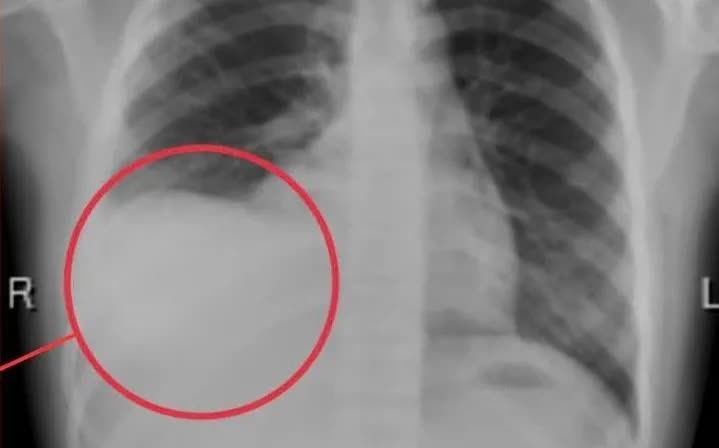

Qua thăm khám và xét nghiệm cận lâm sàng, các bác sĩ phát hiện bệnh nhi bị tràn dịch màng phổi phải lượng nhiều, gây chèn ép, làm xẹp một nửa phổi bên phải và dẫn tới suy hô hấp - một tình trạng nguy kịch nếu không được xử trí kịp thời. Ngay sau đó, bệnh nhi được tiến hành chọc hút, dẫn lưu 600ml dịch màng phổi, giúp cải thiện tình trạng hô hấp.